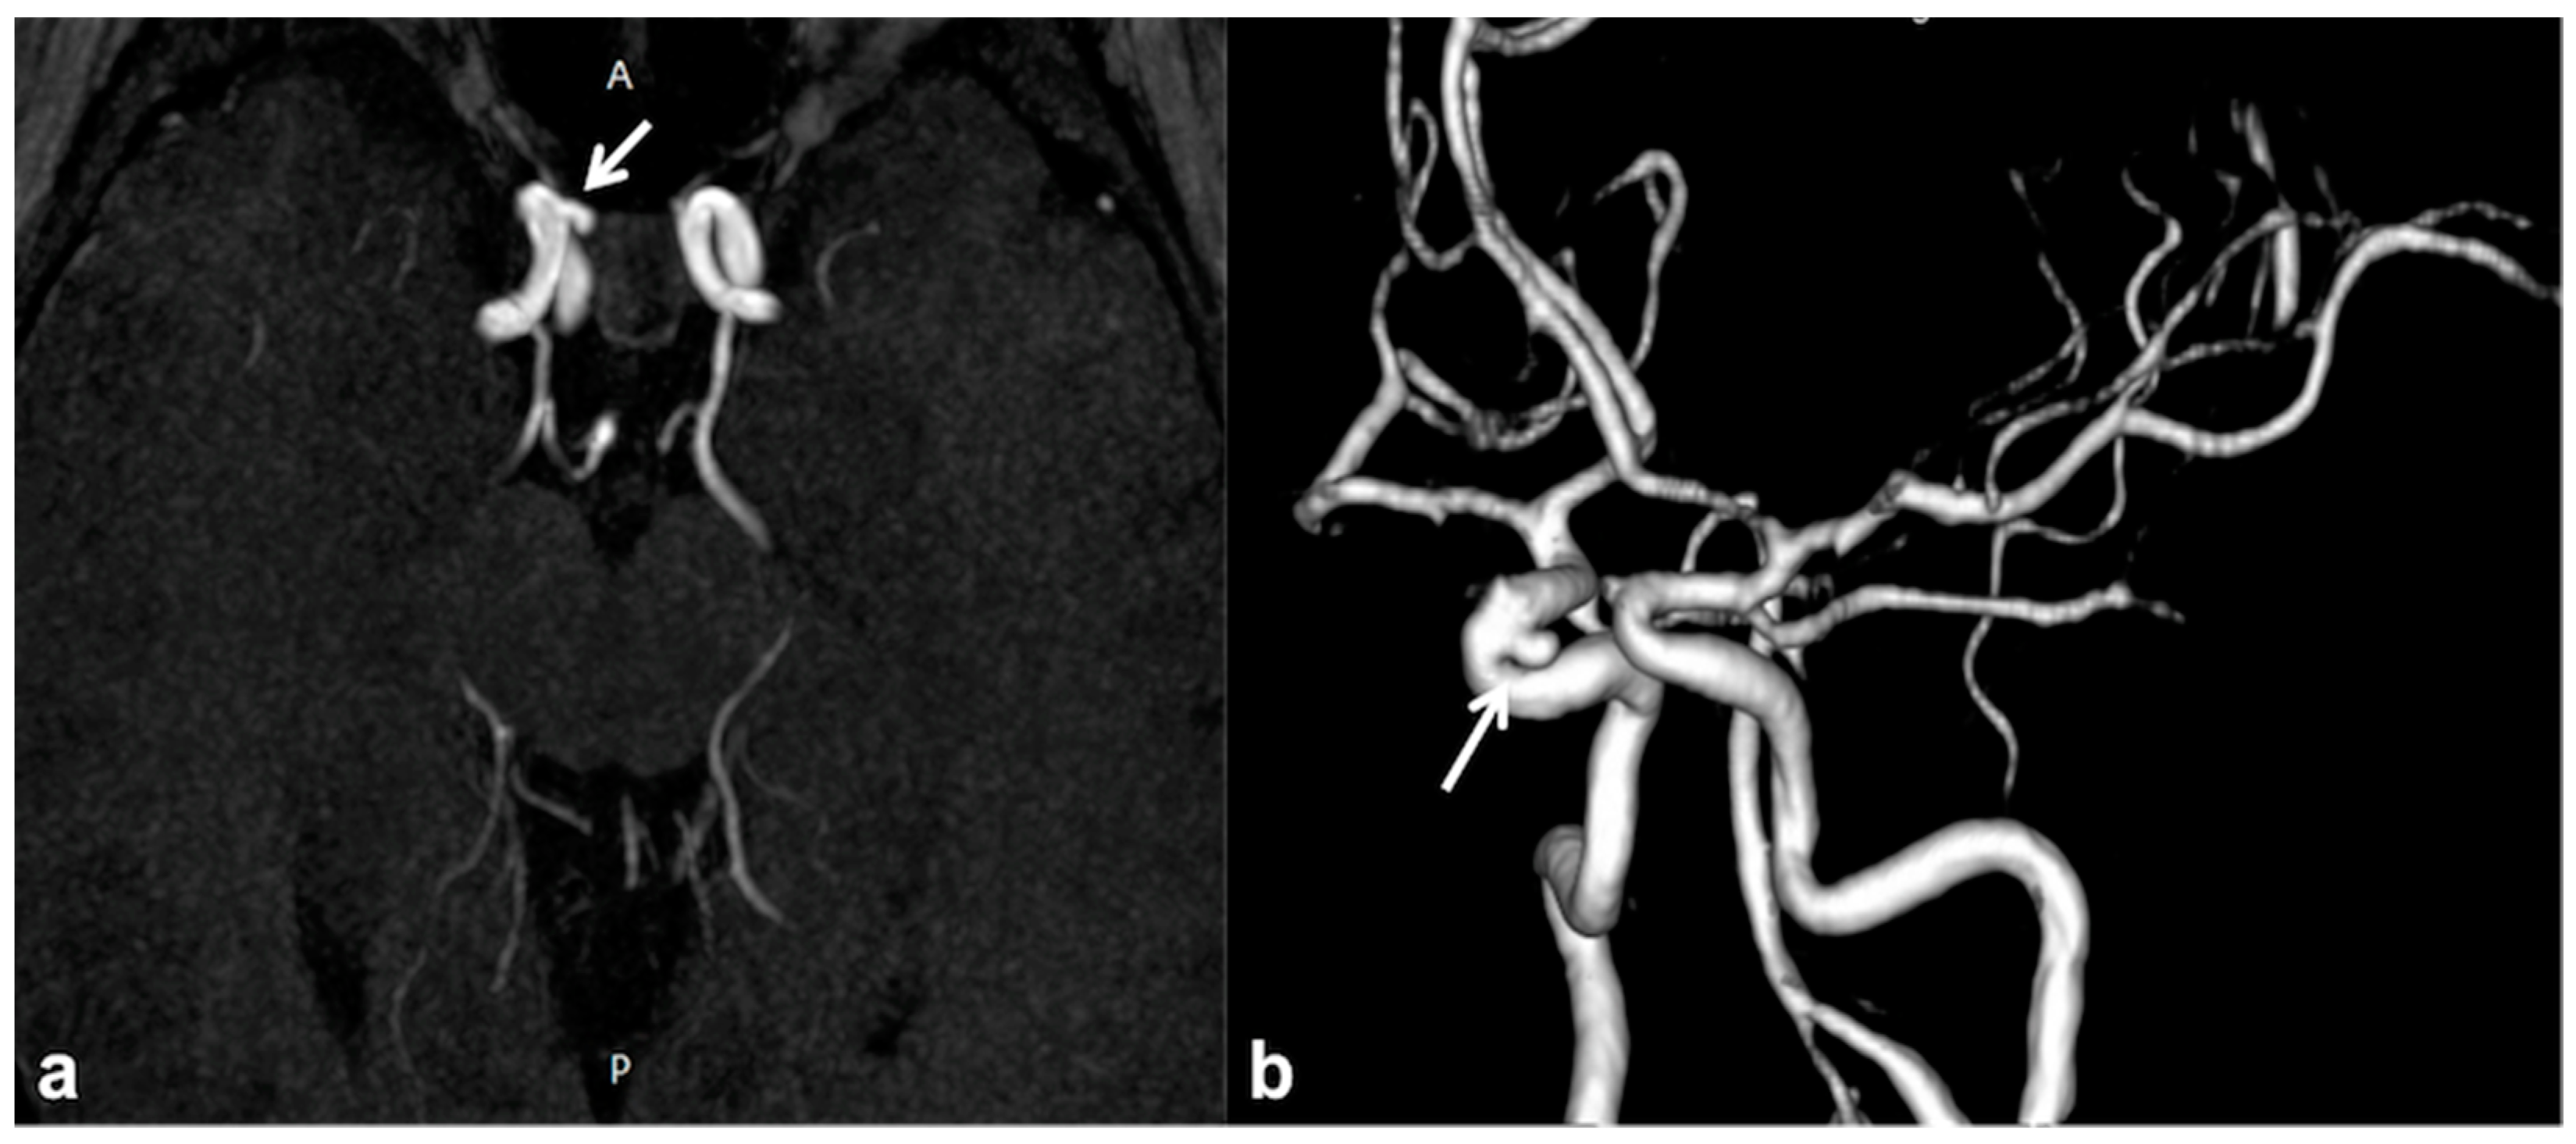

2.5. CNS Vascular Manifestations of NF1

- Kaas, B.; Huisman, T.A.G.M.; Tekes, A.; Bergner, A.; Blakeley, J.O.; Jordan, L.C. Spectrum and Prevalence of Vasculopathy in Pediatric Neurofibromatosis Type 1. J. Child. Neurol. 2012, 28, 561–569. [Google Scholar] [CrossRef]

- Schievink, W.I.; Riedinger, M.; Maya, M.M. Frequency of incidental intracranial aneurysms in neurofibromatosis type 1. Am. J. Med. Genet. Part A 2005, 134A, 45–48. [Google Scholar] [CrossRef] [PubMed]

- Cairns, A.G.; North, K.N. Cerebrovascular dysplasia in neurofibromatosis type 1. J. Neurol. Neurosurg. Psychiatry 2008, 79, 1165–1170. [Google Scholar] [CrossRef] [PubMed]

- Barreto-Duarte, B.; Andrade-Gomes, F.H.; Arriaga, M.B.; Araujo-Pereira, M.; Cubillos-Angulo, J.M.; Bruno Andrade, B. Association between neurofibromatosis type 1 and cerebrovascular diseases in children: A systematic review. PLoS ONE 2021, 16, e0241096. [Google Scholar] [CrossRef] [PubMed]

- Santoro, C.; Giugliano, T.; Kraemer, M.; Torella, A.; Schwitalla, J.C.; Cirillo, M.; Melis, D.; Berlit, P.; Nigro, V.; Perrotta, S.; et al. Whole exome sequencing identifies MRVI1 as a susceptibility gene for moyamoya syndrome in neurofibromatosis type 1. PLoS ONE 2018, 13, e0200446. [Google Scholar] [CrossRef] [PubMed]

- D’Amico, A.; Ugga, L.; Cocozza, S.; Giorgio, S.M.D.A.; Cicala, D.; Santoro, C.; Melis, D.; Cinalli, G.; Brunetti, A.; Pappatà, S. Multimodal evaluation of the cerebrovascular reserve in Neurofibromatosis type 1 patients with Moyamoya syndrome. Neurol. Sci. 2021, 42, 655–663. [Google Scholar] [CrossRef]